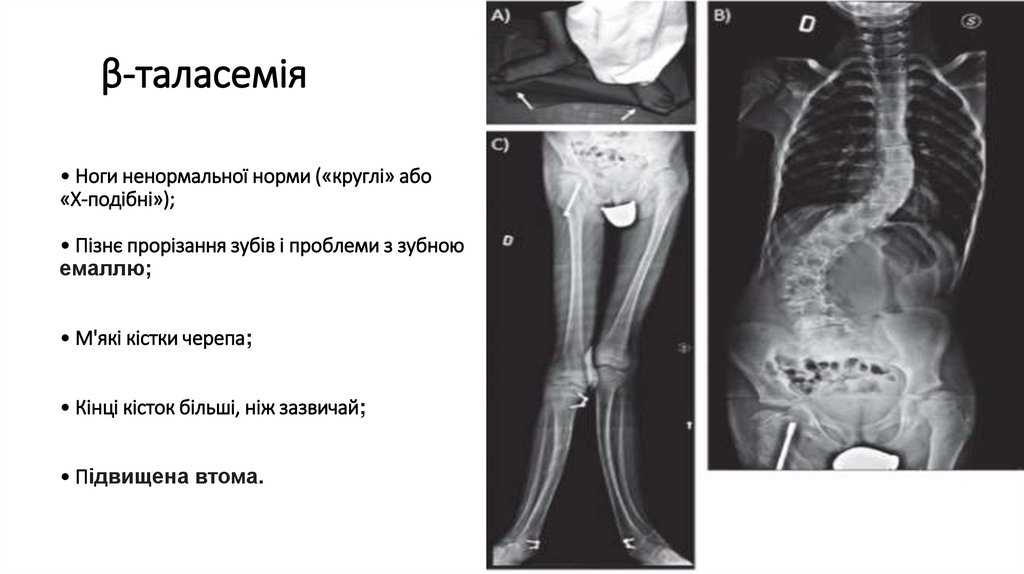

β-таласемія

• Ноги ненормальної норми («круглі» або

«X-подібні»);

• Пізнє прорізання зубів і проблеми з зубною

емаллю;

• М'які кістки черепа;

• Кінці кісток більші, ніж зазвичай;

• Підвищена втома.